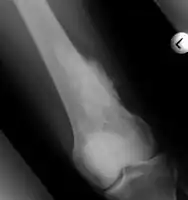

Medical imaging usually shows a well-defined wide-based bony growth on the surface of bone.[5] It can be pedunculated and irregular, giving it a "bizarre" appearance, and is not connected to underlying bone.[2]

MRI mid-upper arm -